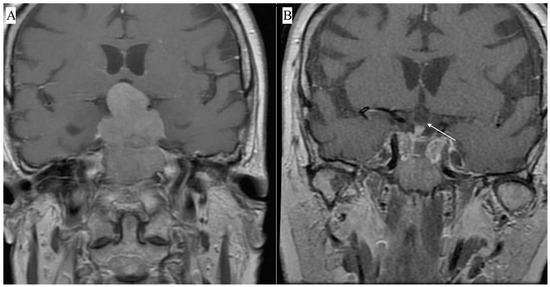

Patients were asked to complete the Polish versions of three questionnaires (SF-36v2, PSQI, and ESS) before surgery and 7.5 months (±1.5 months) after PA resection. The questionnaires were completed using pencil and paper. The study was approved by the local ethics committee. Licenses for the questionnaires were obtained from the appropriate institutions. Of 55 consecutive patients scheduled for TSS due to primary radiological and endocrinological diagnosis of a pituitary adenoma, consent was obtained from 43 individuals. All TSSs were performed by a single experienced neurosurgeon. Patients received endocrinological and ophthalmological care before and after the operation. Magnetic resonance imaging (MRI) was performed before and within 9 months after surgery. Figure 1 shows an exemplary MRI of the parasellar region in a patient with pituitary macroadenoma.

Figure 1. Contrast-enhanced MRI showing a macroadenoma penetrating into the suprasellar region and compressing the optic chiasm. Preoperative T1—weighted contrast-enhanced coronal view (A), postoperative T1—weighted contrast-enhanced coronal view. The white arrow indicates the optic chiasm visible after tumor resection (B).